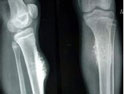

骨巨細胞瘤在1940年首次被Jaffe發現,為常見的原發性骨腫瘤之一,來源尚不清楚,可能起始于骨髓內間葉組織。骨巨細胞瘤具有較強侵襲性,對骨質的溶蝕破壞作用大,極少數有反應性新骨生成及自愈傾向,可穿過骨皮質形成軟組織包塊,刮除術后復發率高,少數可出現局部惡性變或肺轉移(即所謂良性轉移)。骨巨細胞瘤為低度惡性或潛在惡性的腫瘤。本病多在20~50歲發病,女性高于男性。骨巨細胞瘤的原發部位多發生在骨骺,隨病灶的擴大逐漸侵及干骺端。骨巨細胞瘤多侵犯長骨,以股骨下端及脛骨上端為最多。